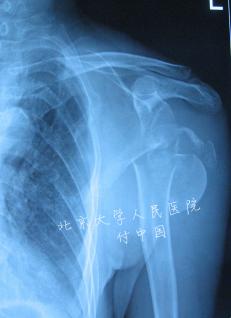

| 说明: | 四部分骨折中可见大、小结节骨折移位超过1cm,头脱位或成角畸形超过45°。此类骨折头坏死率较高 |